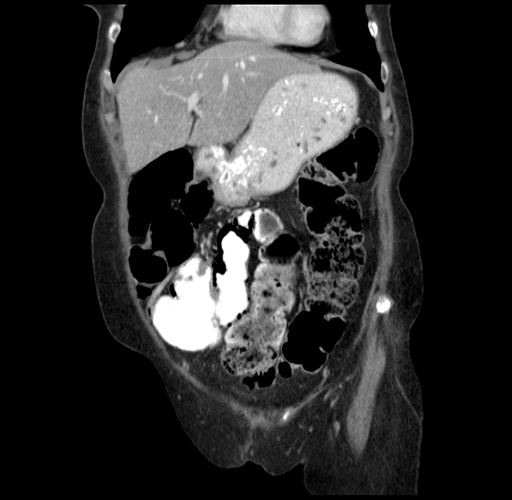

Pre-Chemo: Coronal Venous